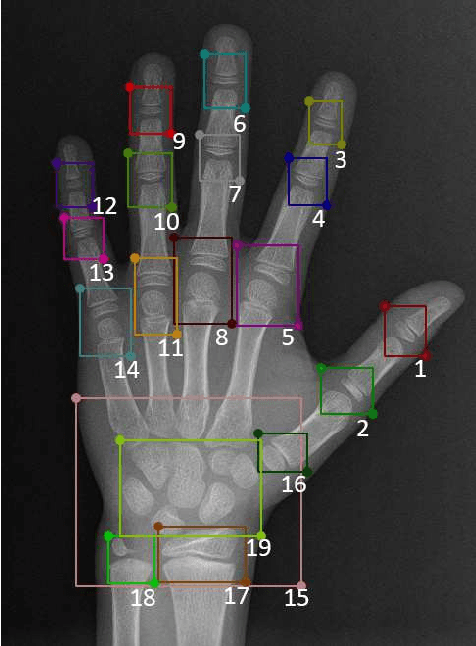

Abstract:The bone age, reflecting the degree of development of the bones, can be used to predict the adult height and detect endocrine diseases of children. Both examinations of radiologists and variability of operators have a significant impact on bone age assessment. To decrease human intervention , machine learning algorithms are used to assess the bone age automatically. However, conventional supervised deep-learning methods need pre-labeled data. In this paper, based on the convolutional auto-encoder with constraints (CCAE), an unsupervised deep-learning model proposed in the classification of the fingerprint, we propose this model for the classification of the bone age and baptize it BA-CCAE. In the proposed BA-CCAE model, the key regions of the raw X-ray images of the bone age are encoded, yielding the latent vectors. The K-means clustering algorithm is used to obtain the final classifications by grouping the latent vectors of the bone images. A set of experiments on the Radiological Society of North America pediatric bone age dataset (RSNA) show that the accuracy of classifications at 48-month intervals is 76.15%. Although the accuracy now is lower than most of the existing supervised models, the proposed BA-CCAE model can establish the classification of bone age without any pre-labeled data, and to the best of our knowledge, the proposed BA-CCAE is one of the few trails using the unsupervised deep-learning method for the bone age assessment.